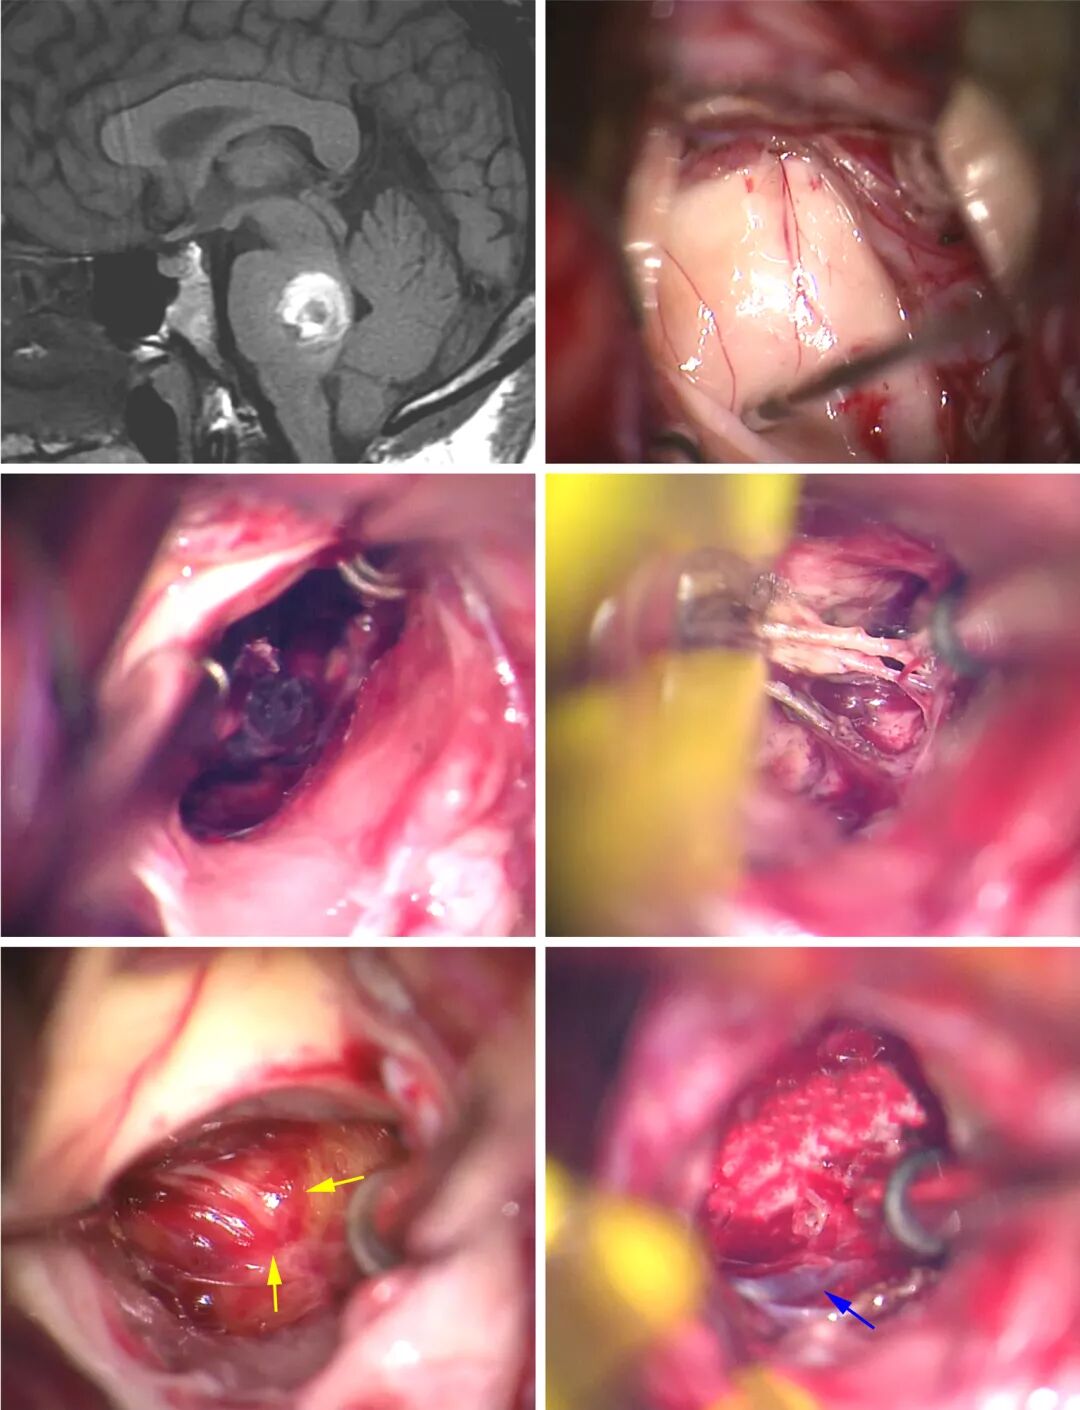

图6:显露CM后,用吸引器或垂体咬骨钳清除CM内与周围的血肿(A)。然后游离小的供血动脉,电凝并切断(B)。推移减压的病灶囊与胶质边缘分开(C )。仔细保护DVA,与病灶分开(D)。

图7:这个桥脑后部的CM经膜髓帆入路到达,在第四脑室底刺激描记面丘(上排的照片)。清除血肿可创造额外的空间;电凝并切断供血动脉(中排)。然后将病灶囊从手术残腔的胶质壁上钝性分离下来(黄色箭号),在切除结束时保留DVA(蓝色箭号)(下排)。

以下步骤描述经膜髓帆入路切除桥脑后部的CM。